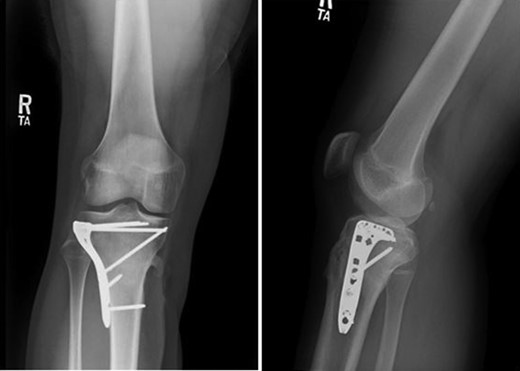

Patient is a 14-year-old male who slipped and fell while jumping off of a diving board and landed onto a flexed right knee. The patient was stable on presentation and neurovascularly intact with the knee locked in flexion. Skin was tenting anteriorly over the tibial tubercle and his compartments were swollen but compressible. A single plain film view (Fig. 1) was obtained prior to orthopaedic consultation. Closed reduction under sedation and splitting was attempted in the ED with partial but unsatisfactory improvement. Post-reduction radiographs (Fig. 2) demonstrated a tibial tubercle fracture with extension through the entire proximal tibial physis with metaphyseal involvement posteromedially. We classified this as a type IV tibial tubercle fracture, Salter–Harris II variant. In conjunction with patient and family we planned for urgent closed versus open reduction and application of knee-spanning external fixator. Immediately prior to surgery in the pre-operative holding area, the patient noted increasing right leg pain. In the operating room (OR), a marked increase in swelling with tense skin was observed. Due to rapidly progressive swelling and nature of the fracture, the decision was made to proceed with a 4-compartment fasciotomy of the right leg. The medial-sided fasciotomy (Fig. 3) revealed significant bulging of the superficial and deep compartments; however, the anterior and lateral compartments were less swollen. The fracture was unable to be closed reduced intraoperatively, therefore proximal extension of the medial fasciotomy wound was performed to open and reduce the fracture under direct visualization. Anatomic reduction was achieved and a knee-spanning external fixator was applied (Fig. 4). Approximately 72 hours later the patient was brought back to the OR for irrigation and debridement, lateral wound closure, and medial wound vacuum placement. Another 72 hours later, he returned to the OR for removal of the external fixator, ORIF, and split-thickness skin grafting of the medial fasciotomy site. An anterolateral approach was used with a 3.5 mm proximal tibial locking plate (Fig. 5). At most recent follow-up (Fig. 6), six months post-op, the patient is pain free, ambulating without assistive device, and has returned to all desired activities.

Outcomes following appropriately managed tibial tubercle fractures have generally been excellent. Pretell-Mazzini et al. [6] conducted a systematic review of 325 patients with tibial tubercle fractures. They reported a 99.4% rate of radiographic union rate with 98% returning to preinjury activity levels with full range of motion. Pace et al. [2] reported 100% fracture healing with no growth disturbances in his series of 24 patients with type IV tibial tubercle fractures. In this case, subsequent radiographs have demonstrated fracture union without hardware complications.